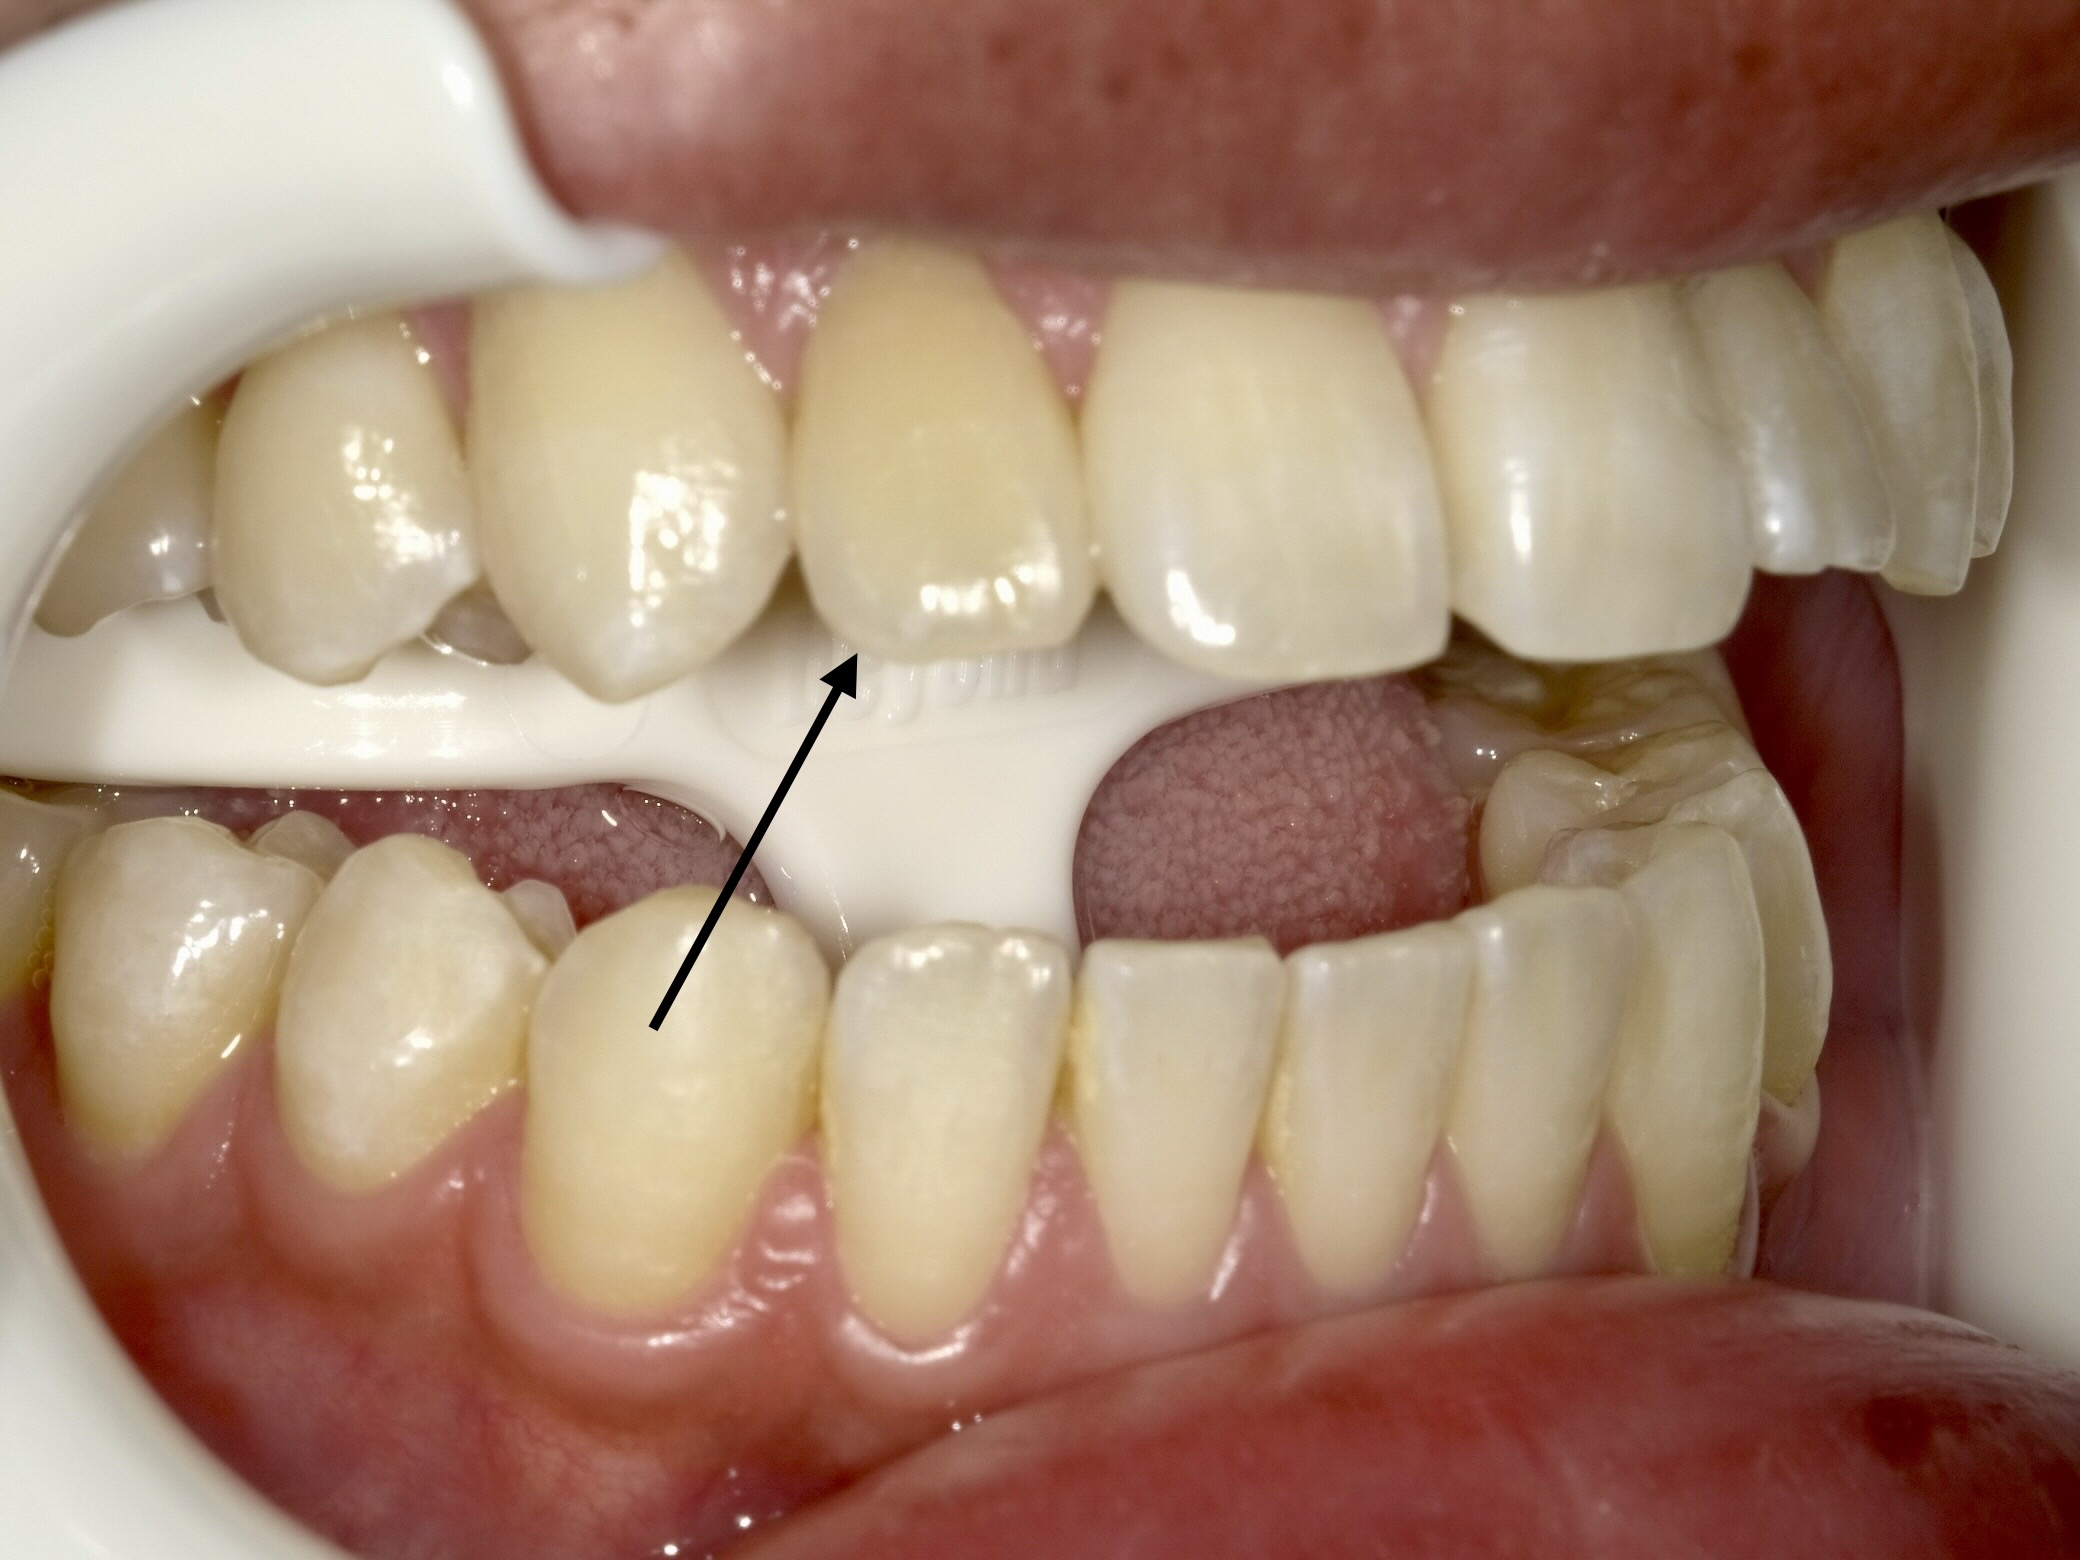

【Before】(矢印が神経のない変色歯)全体をホワイトニングしてベースを明るくします。

【After】セラミッククラウン装着。どこを治療したか分からないほど馴染んでいます。

- 治療方法:セラミッククラウン法 + オフィスホワイトニング

- 治療期間:約1ヶ月 / 費用:¥220,000(税込)

- リスク:歯を削る必要があります。